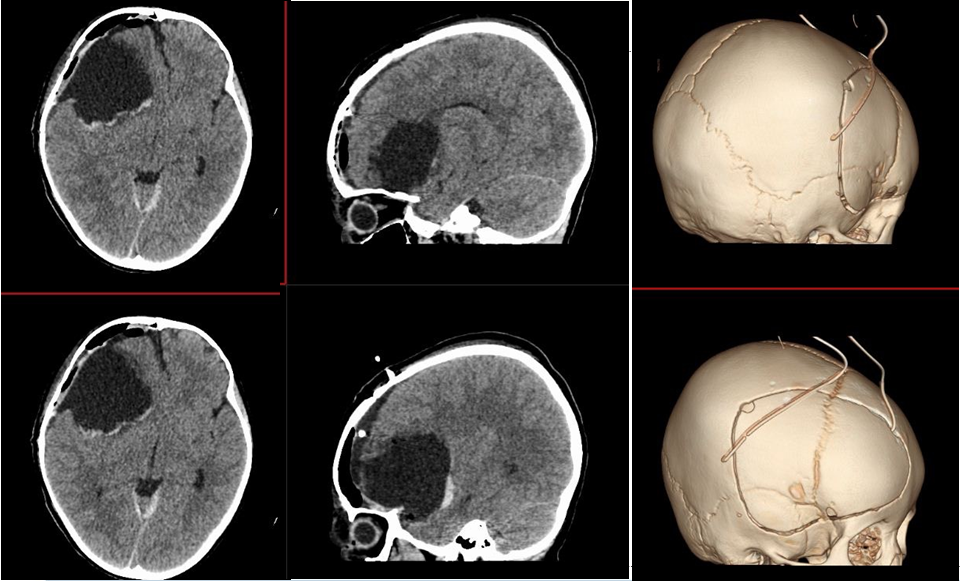

术前影像

术前颅脑CT囊实性占位